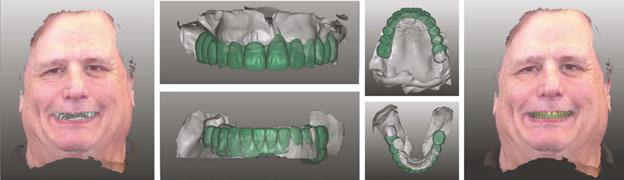

The protocol for immediate loading of fullarch implants includes the extraction of all non-salvageable teeth, implant placements, abutment placements, intraoral scans (Itero®) with scan bodies placed on the abutments, and in-house milling (Zirconzahn®) on the day of the surgery. The information referred to the esthetics, and vertical dimension is gathered with the extraoral 3D facial scans with Face Hunter software (Zirconzahn), 2D photographs, and intraoral scans prior to surgery. The day of extractions and implant surgery, abutments are placed and scanned, and initial designs are merged with anatomical landmarks. The polymethyl methacrylate (PMMA) prosthesis is milled in-house following the merging of the initial and post-implant placement digital scans and the design of the new teeth the day of the surgery.

Dr. Siranli starts by analyzing the patient’s facial esthetics to design a personalized smile and then combine 3D facial and dental scans (Figure 1).

Patient’s resting and smiling incisal display, vertical dimension of occlusion, and intraoral maximum intercuspation are evaluated clinically and through Face Hunter software (Zirconzahn®) prior to the surgery (Figures 2-4). A detailed smile design prescription gets created after this point. In this particular case presentation, the smile design prescription was:

• Bring the maxillary incisal edge down 8 mm.

• Bring the mandibular incisal edge down 4 mm.

• Bring the mandibular bone level down 5 mm.

• Labiolingually, use mandibular anterior as a guidance.

• Open the vertical dimension of occlusion 6 mm.

Figure 1: Face Hunter 3D facial scans merged with intraoral scans. Green color represents the new digital design of the smile design Figures 2-4: 2. Resting incisal display. 3. Smiling incisal display. 4. Maximum intercuspation Figure 5: Implants, multi-unit abutments, and scan bodies placed Figure 6: Post-surgery intraoral scans

Figure 7: Milled PMMA Figure 8: Inserted PMMA on the day of the surgery. Figure 9: Patient’s pre- and postoperative pictures Figure 10: Dr. Samantha Siranli (prosthodontist), Tony Yoo (CAD/CAM specialist), Shyun Oh (master ceramist)